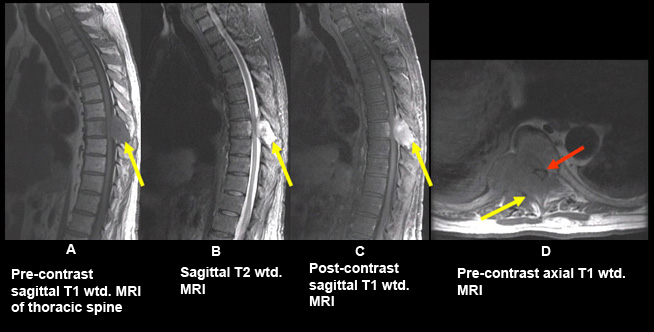

Findings:

Bony metastasis involving the T8 vertebral body, right pedicle/transverse process and spinous process (yellow arrows in A,B,C,D) with epidural tumor producing marked degree of cord compression (red arrow).

Final impression

- Bony metastasis from renal cell carcinoma with epidural tumor producing cord compression